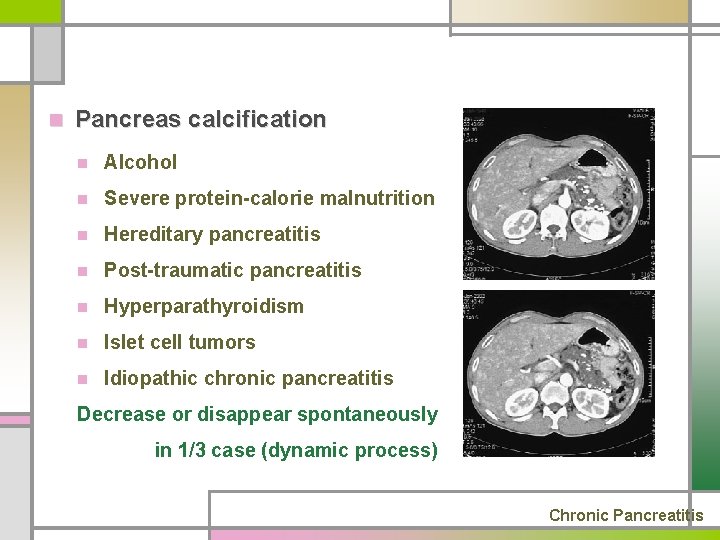

n Pancreas calcification n Alcohol n Severe protein-calorie malnutrition n Hereditary pancreatitis n Post-traumatic pancreatitis n Hyperparathyroidism n Islet cell tumors n Idiopathic chronic pancreatitis Decrease or disappear spontaneously in 1/3 case (dynamic process) Chronic Pancreatitis